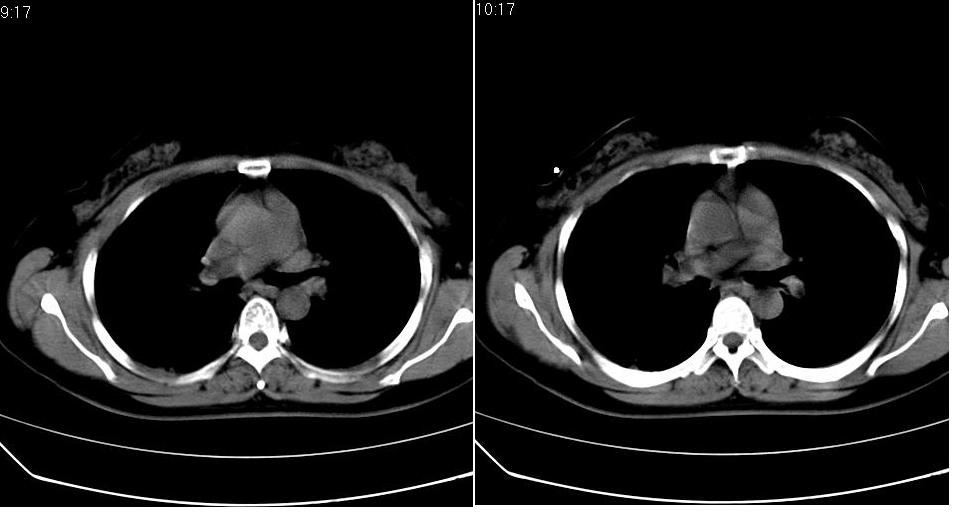

女 40岁,胸片体检发现右肺肿块,无任何症状。

下叶背段多发性小腺泡结节,考虑结核。

肺动静脉瘘可考虑,建议增强

考虑右肺下叶背段继发性肺结核。